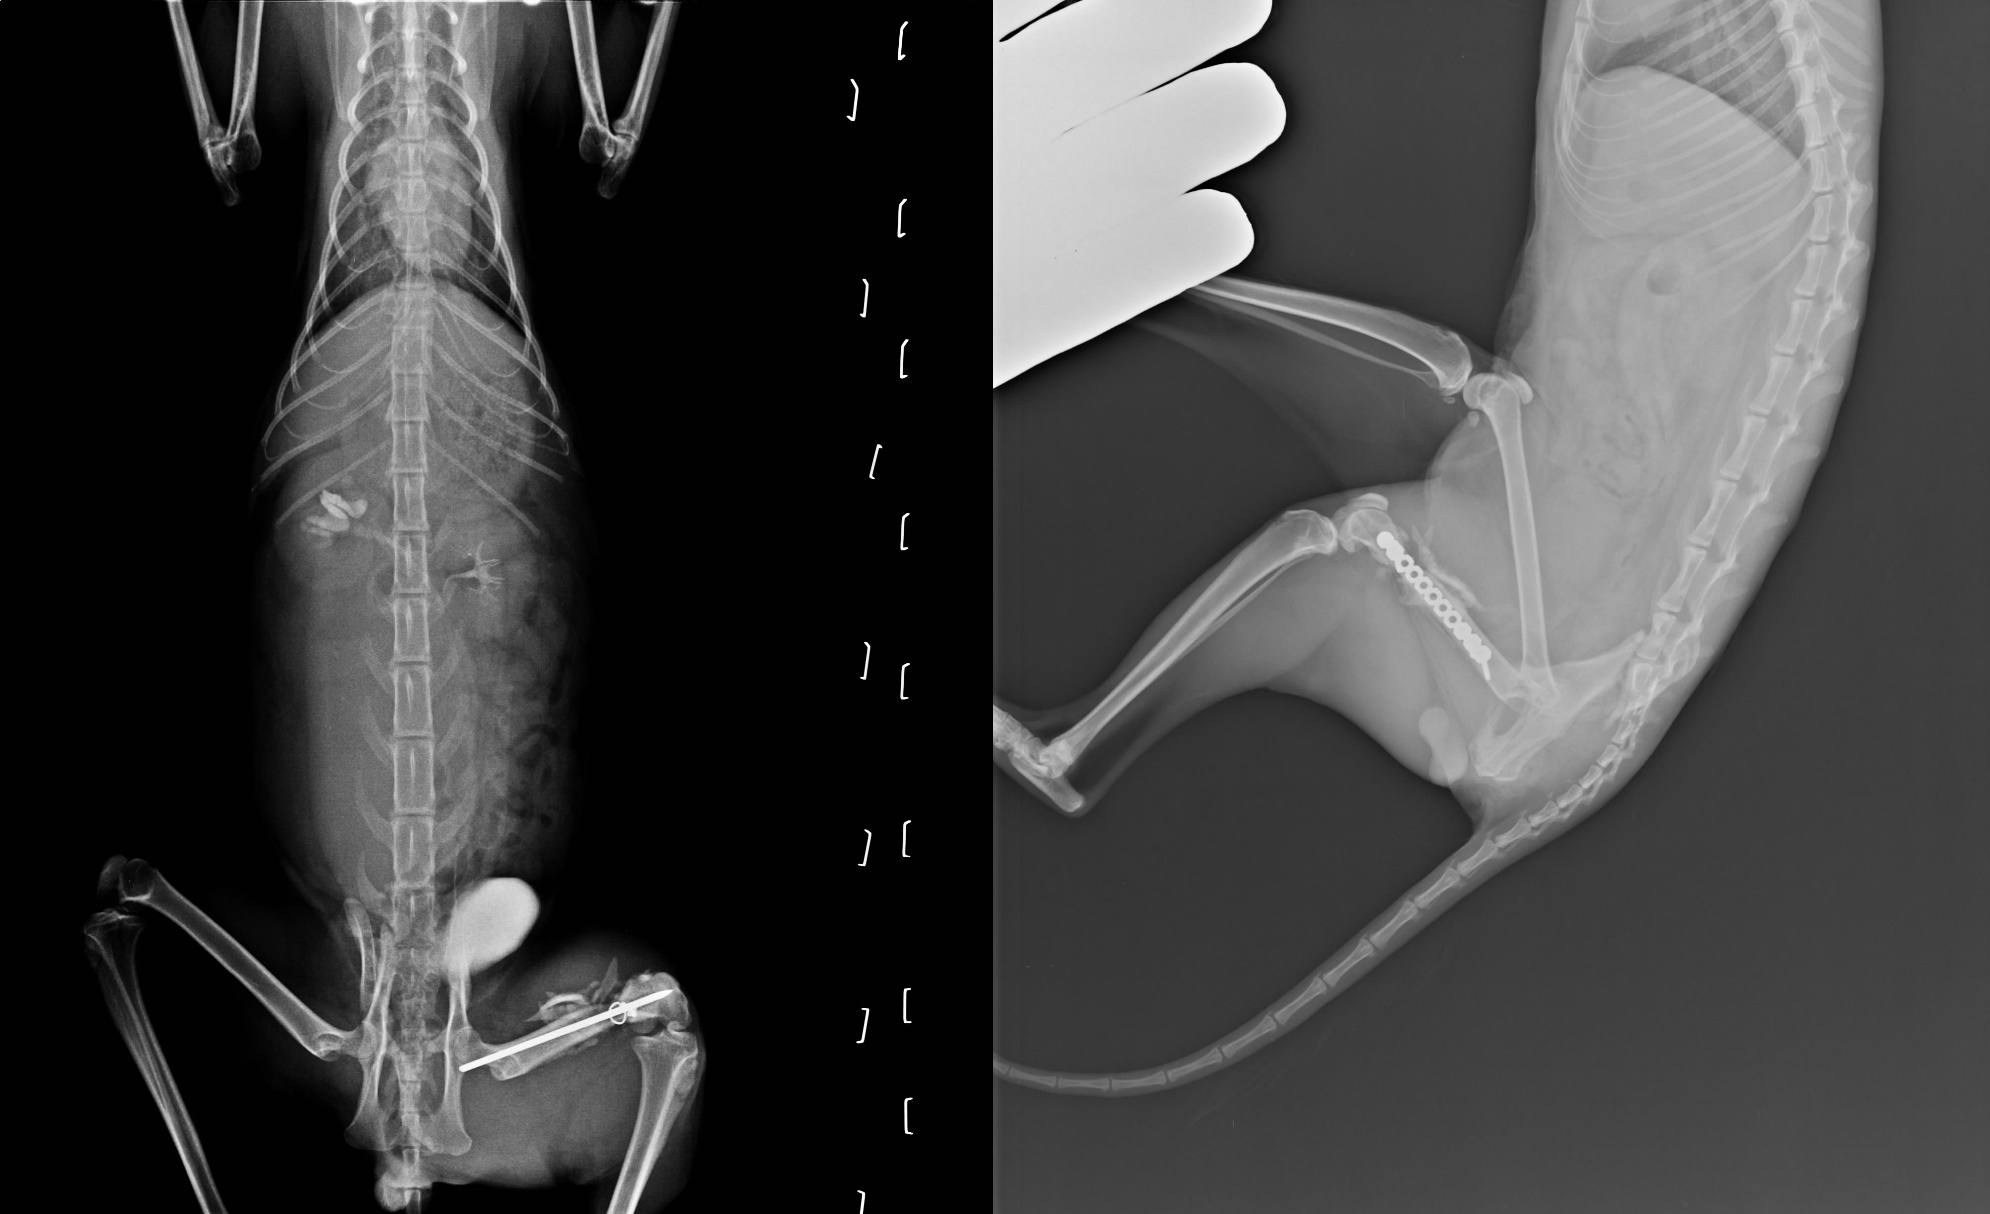

- 編號: 3240

主題: 車禍大腿骨折腎臟輸尿管斷裂 申請者姓名: 臺北市支持流浪貓絕育計劃協會 花色: 申請日期: 2013-11-21 16:13:40 申請者部落格: 申請者臉書網址: 所在縣市/合作醫院: 台北市/極光動物醫院 治療費用: 88990元 需求人數: 92人 已結案 (2014-01-10 17:55:52) 報名人員: Patrick x2(已付款)、Hung(已付款)、Queenie(已付款)、悅萱 x5(已付款)、Eason(已付款)、Monica Wang(已付款)、Larry Shen(已付款)、Bei Bei Wang(已付款)、vivian(已付款)、Kimi Huang(已付款)、Ou Han x2(已付款)、Kiki Liang(已付款)、李真(已付款)、Eva Wen(已付款)、余蛋娘(已付款)、安榭(已付款)、Joba Huang(已付款)、貓空(已付款)、RitaPeng x2(已付款)、Fei Su x3(已付款)、philip x2(已付款)、Grace Luo(已付款)、yuki x5(已付款)、Lee Jing Yi(已付款)、miraai(已付款)、Jessica Wu(已付款)、Cindy Chen(已付款)、Patricia Hsiao(已付款)、劉明玲(已付款)、櫻花妹(已付款)、如絲(已付款)、Wendy x3(已付款)、apin(已付款)、Eason(已付款)、貓公會淡水海貓分部 x4(已付款)、Shan Chou x3(已付款)、Yao-Hsien Tseng x2(已付款)、Nora Chu、stella x2(已付款)、夢東橋(已付款)、Emily Chou(已付款)、林 ミドリ(已付款)、陳噗奇(已付款)、Ava(已付款)、Jocelyne YuYu Kao、Chafia(已付款)、Ppn Huang(已付款)、Jiens Yu(已付款)、Jocelyne YuYu Kao、Jocelyne YuYu Kao x2、Jocelyne YuYu Kao x3、Jocelyne YuYu Kao x3(已付款)、Jocelyne YuYu Kao x4、ERic YU(已付款)、Patrick x2(已付款)、Fenny Hsu(已付款)、康寶(已付款)、Wang Mu(已付款)、meemee(已付款)、Connie(已付款)、Vincent Ho(已付款)、林韋韋(已付款)、Eucalyptus Wu(已付款)、BEAN(已付款)、Jasmine Lin(已付款)、文祥(已付款)、Michelle Chou(已付款)、lavinia x4(已付款)、Tiffany Shen(已付款)、 候補人員: 動物病情說明: 新北幅員遼闊,各式各樣的貓咪狀況都有,

當時收容所醫生已先行替大腿骨折的他做了固定手術,

但骨盆腔斷裂的疼痛,

讓這隻有著美麗美短紋的白底虎斑貓,

根本無法站立只能一直大聲鳴叫。

原來以為Seven只剩下骨盆腔斷裂問題需處理,

因為照X光後,發現他的膀胱異常腫脹,

看來已無法自行排尿,

再晚一步就可能破裂、命危在旦夕…

顯影劑照影發現原本安置在腎臟連接膀胱的輸尿管斷裂在內,

接到後腹腔造成發炎,緊急進行導尿,三天內,還必需立即進行摘腎手術保命!

摘腎之後,Seven亂叫的情況好多了,

情緒穩定不少,但在收容所進行的骨折手術,

因為骨釘鬆落、出現發炎的現象,

除了給予抗生素之外,醫師考慮重新手術使用特殊的骨板進行固定,

兩週後Seven狀況穩定後就立刻進行骨折骨板手術,

術後給予嗎啡貼片止痛,過程很順利,

現在Seven已經可以站立與自由行走,

至於骨盆腔部份則需要時間讓骨頭癒合,

在半年內都不宜跳上、跳下,